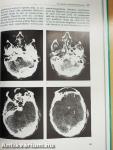

Traumatologie des Hirn- und Gesichtsschädels

Megjegyzés: 2. kiadás. További kapcsolódó személyek a kötetben. Színes és fekete-fehér fotókkal, fekete-fehér ábrákkal.

Ein Schädelbruch gilt als bedrohliche Verletzung. Tatsächlich aber sind weniger der Knochenbruch als vielmehr die ihn begleitenden Hirn-, Gesichtsschädel- und andere Weichteilverletzungen gefährlich. Oft werden diese Begleitverletzungen des Gesichtes, der Augen oder der Nasennebenhöhlen und ihre Komplikationen verkannt.

In diesem praxisnahen Buch wird der Versuch unternommen, die durch Gewalteinwirkung auf den Gesamtschädel entstehenden vielfältigen Verletzungsformen aus neuro- und kieferchirurgischer, aus otorhinologischer und ophthalmologischer Sicht gemeinsam zu besprechen. Somit stellt das Buch für alle mit der Behandlung Schädel-Hirn-Verletzter Befaßten einen Leitfaden dar, in dem nicht die Grenzen der verschiedenen Fachgebiete aufgezeigt werden, sondern der Blick über sie hinweg zum früh- und rechtzeitigen Konsil des anderen Fachgebietes motivieren soll.